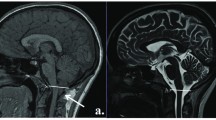

Therefore, despite eliminating the effect of possible covariates on the cognitive performance of both groups, differences between the CM-I group and the control group were observed in nine of the initially proposed variables (Fig. 1). The results are included in Table 3 along with the corresponding effect size for each variable. As an additional illustrative example, Fig. 2 shows the execution of two patients with CM-I in the ROCF. Some visuospatial disorganization is noticed in the precision of copy, as well as a poor execution in visual memory.